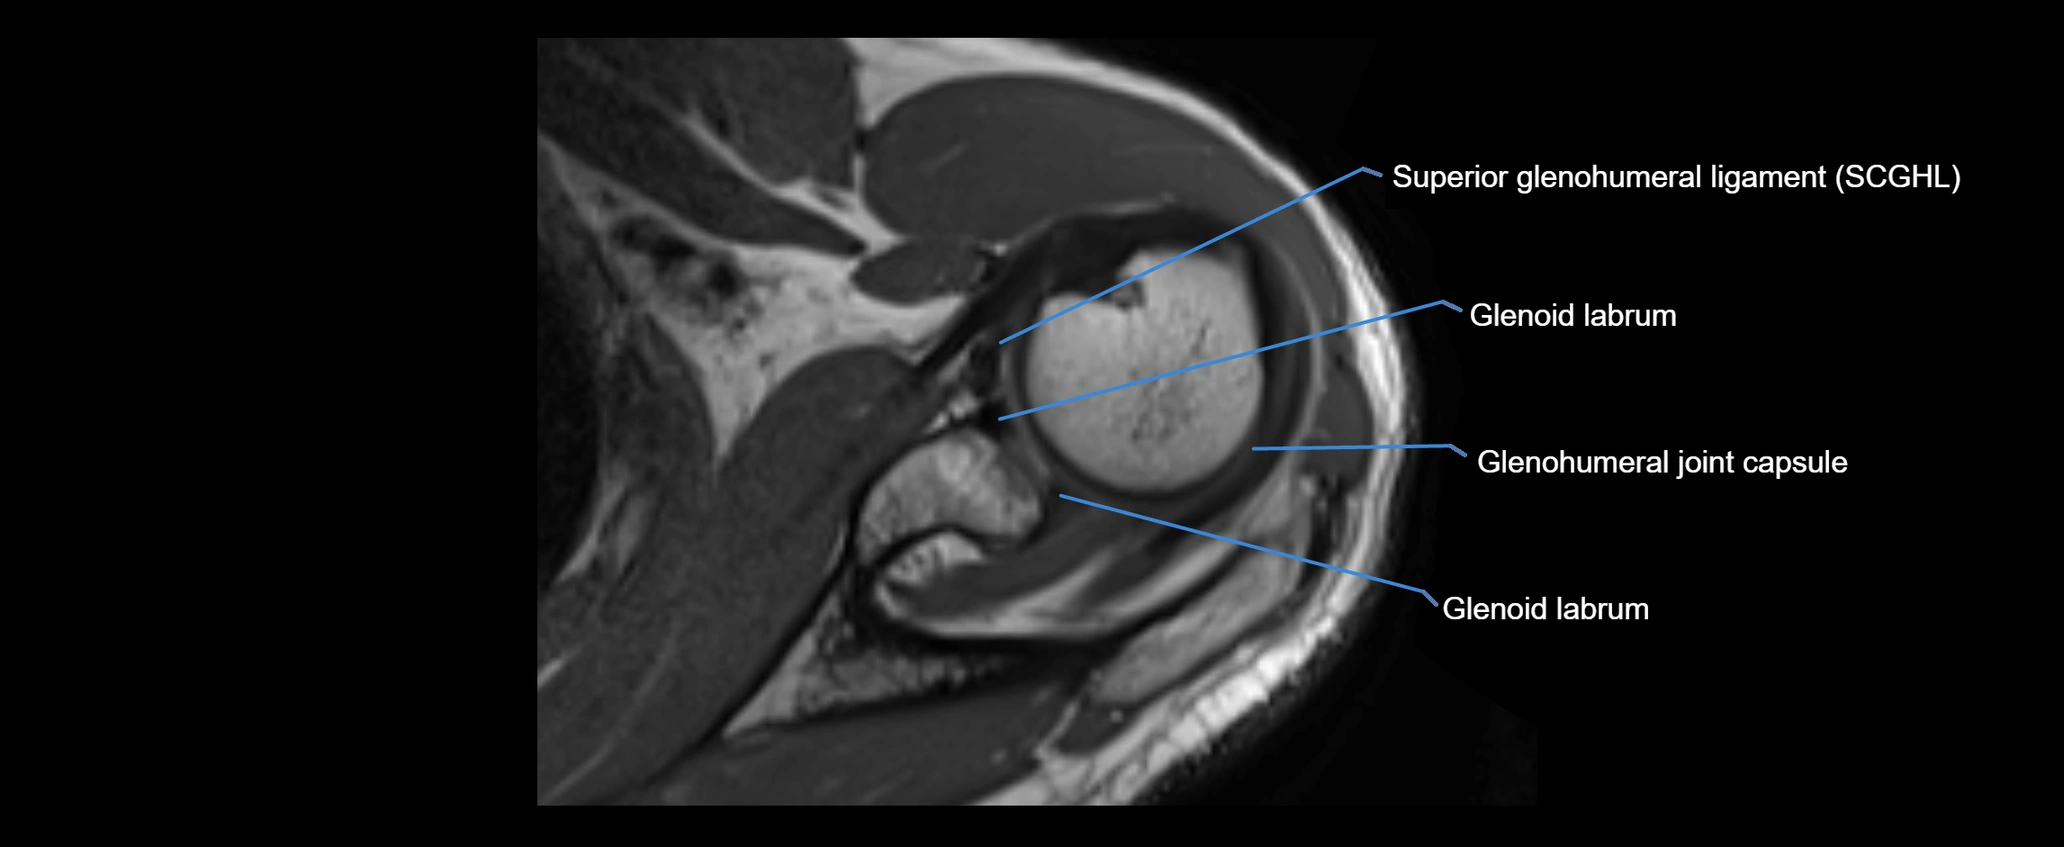

MRI images

image